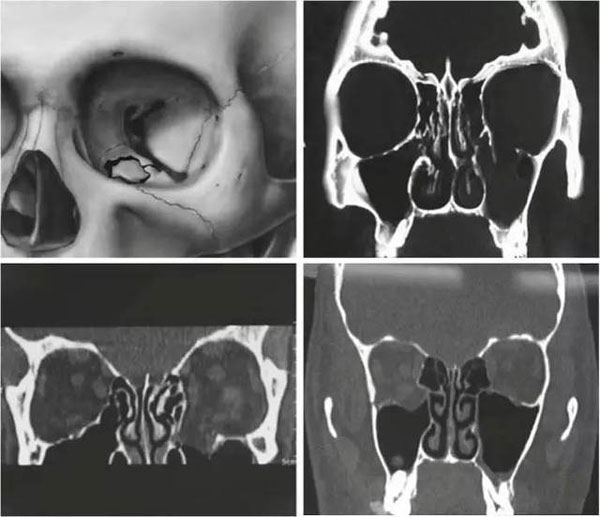

近年來,隨著工業(yè)外傷和交通事故發(fā)生率的增加,眼眶骨折的患者越來越多。眼眶壁骨質(zhì)薄弱,發(fā)生骨折后容易產(chǎn)生骨質(zhì)缺損,需要使用生物材料替代缺損的骨組織,來重建眼眶結(jié)構(gòu)。

過去用于修復(fù)眼眶的材料主要有自體骨、羥基磷灰石、生物活性玻璃和硅膠等,但都存在不同程度的缺陷,容易產(chǎn)生移位、感染等并發(fā)癥。上世紀(jì)90年代初,鈦合金開始應(yīng)用于眶壁骨折缺損的修復(fù),并因其優(yōu)異的特性而備受青睞。

自1990年鈦網(wǎng)首次成功應(yīng)用于眼眶修復(fù)以來,鈦網(wǎng)作為填充和內(nèi)固定材料被應(yīng)用于眶壁、眶底缺損的修復(fù)。但鈦網(wǎng)不規(guī)則的形狀和光滑的表面容易被纖維組織包裹,有促進(jìn)炎癥細(xì)胞高密度分布和粘連的可能,并且會引起鄰近骨質(zhì)的溶解。

由于鈦網(wǎng)邊緣銳利且具有一定硬度,當(dāng)手術(shù)切口較小時,鈦網(wǎng)容易被周圍組織阻礙,難以插入預(yù)定的位置,在插入的過程中甚至容易造成醫(yī)源性損傷。此外,由于鈦網(wǎng)較薄,無法糾正眼眶與面中部骨折后期容易發(fā)生的眼球內(nèi)陷。